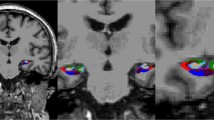

To better understand the relationship between the hippocampus and stroke or cardiovascular risk factors, one must first be aware of the vascular supply to the medial temporal lobe. Szabo et al recently characterized hippocampal stroke and distinguishable phenotypic lesions. They described the following hippocampal vascular supply accordingly to the Stephens and Stilwell atlas source reference: mainly from the posterior cerebral artery (PCA) and to a lesser degree from the anterior choroidal artery (AChA) with the occipital two-thirds being supplied by PCA branches from the P2 segment’s anterior, middle and posterior hippocampal arteries, and the rostral third by branches from the AChA which provide variable supply to the head of the hippocampus [18, 19]. The middle and posterior hippocampal branches supply the body and tail of the hippocampus and the anterior branch supplies the head of the hippocampus and the uncus. Szabo et al showed that there was verbal episodic long-term memory deficit in left and nonverbal episodic long-term memory deficit in right hippocampal infarction in a number of patients after formal neuropsychological examination [18]. A hallmark in the study was that infarcts were not limited to the hippocampus but were more widespread.

Wu et al carried out a MRI brain study of high-resolution functional maps of the hippocampal formation in 240 community-based nondemented persons who had a mean age of 79.7 years, of whom 25 % had type 2 diabetes, and 74 had MRI evidence of brain infarcts [20]. The authors concluded that the hippocampal subregion (dentate gyrus) linked to diabetes was associated with blood glucose level as the pathogenic mechanism and provided a causal pathway for age-related memory decline. Furthermore, the hippocampal region linked to infarction (CA1 region) was associated with transient hypoperfusion as the proposed causal mechanism. The hippocampus has a high concentration of insulin receptors [21]. The Wu et al findings provide a possible neuroanatomical target for testing interventions related to glucose metabolism that might prevent or slow cognitive impairment or decline [20].

The same core group of investigators carried out another study to determine whether brain infarcts and diminished hippocampal volume were independently associated with poorer memory function to suggest that both the integrity of the hippocampus and more diffuse brain networks involved with the hippocampus in memory function were essential [22]. Furthermore, the investigators studied brain infarcts and hippocampal volume in relation to a possible unique profile of cognitive deficits. They showed the following: (1) brain infarcts and hippocampal volume were associated with specific aspects of memory function; (2) brain infarcts were associated with smaller hippocampal volume; and (3) both hippocampal size and presence of infarcts were associated with global memory function [22]. The data support the contention that infarcts may be associated with poor memory function and not just nonmemory performance domains, as was traditionally believed in VCI. Since the hippocampus is part of a network with other areas of the brain involved in memory such as the thalamus, basal forebrain, and amygdala, ischemic injury to these latter neuroanatomical structures could result in abnormal memory processing or performance [22]. In addition, and based on neuropsychological performance profiles, the investigators observed that hippocampal volume was associated with performance on long-term recall, delayed recognition, and delayed free recall; subcortical infarcts with performance on learning, long-term recall and delayed recall; and cortical infarcts with performance on delayed recognition of the selective reminding test. Finally, main results from a brain necropsy study by Arvanitakis et al lends further support to the belief that brain infarcts exert a negative effect on memory function independent of traditional AD pathology such as hippocampal atrophy [23].